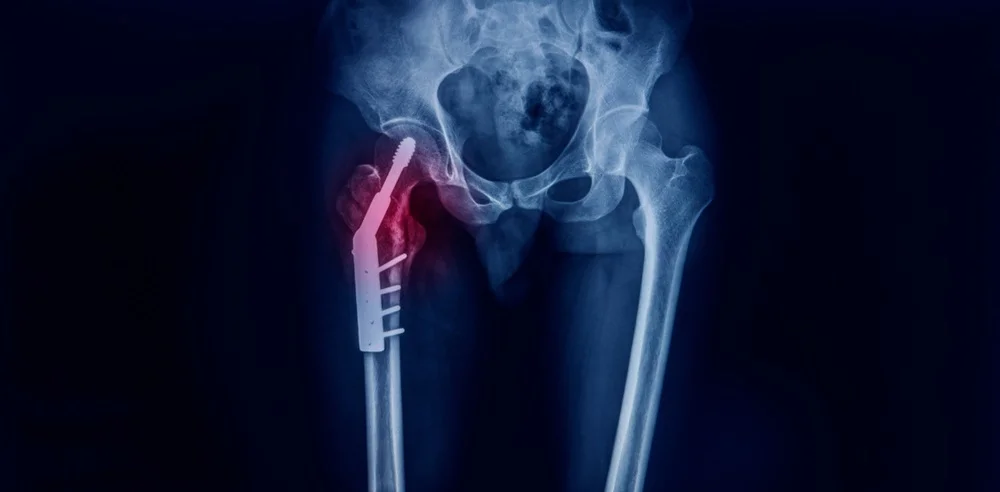

Διατροχαντήριο Κάταγμα Ισχίου

Αφορά το κάταγμα μεταξύ του μείζονα και του ελάσσονα τροχαντήρα, δηλαδή αυτών που ενώνουν τα ισχία με τους μύες του μηρού. Για την αντιμετωπιση, ακολουθείται χειρουργική επέμβαση  με ενδομυελικό καρφί το οποίο τοποθετείται μέσα στο μυελό του οστού από μία μικρή τομή στο ισχίο και μετά σταθεροποιεί το κάταγμα μέσω μιας βίδας.